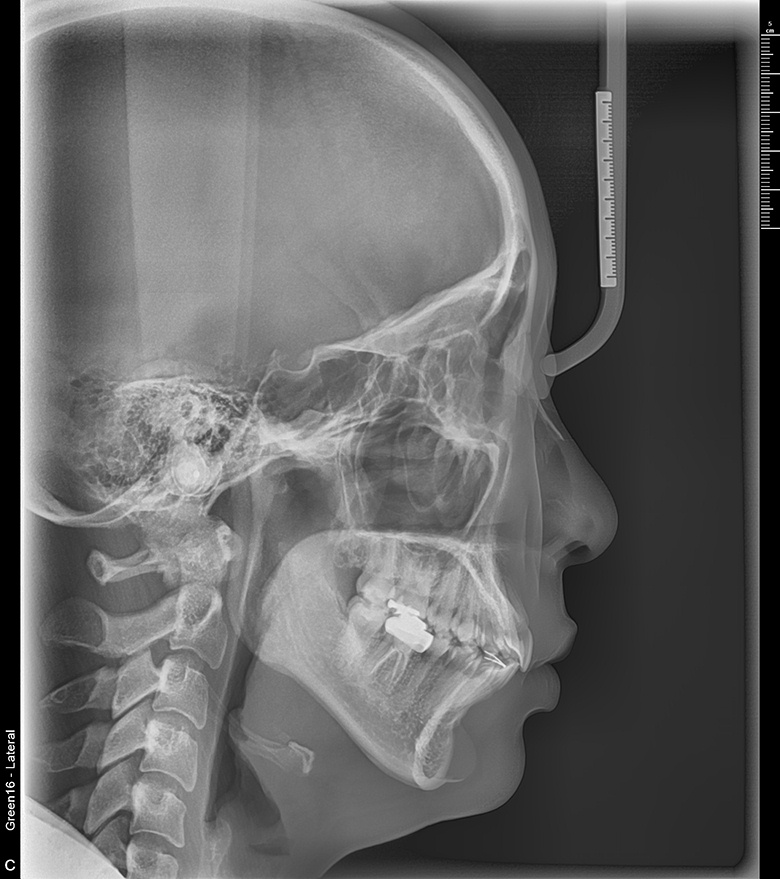

치료 후 사진입니다.